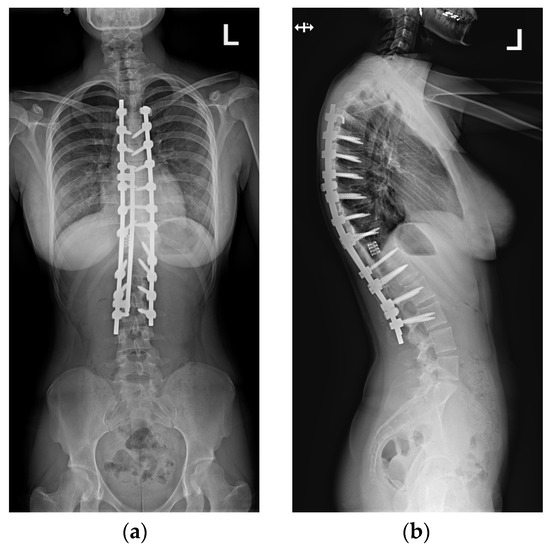

Postoperative imaging showed significant improvement in both three-dimensional planes (Figure 8).

Upon conducting a postoperative physical examination, it was observed that the patient’s shoulder symmetry and rib hump had improved significantly without any neurological or other complications. Figure 9 shows a significant improvement in the patient’s posture, sagittal balance (focal thoracic kyphosis from 108° to 43°), and coronal balance (from 63° to 25°). The patient was discharged 5 days after surgery; no brace was ordered. Figure 10 and Figure 11 show the X-rays and 3D-CT of the patient at the final follow-up.

Figure 8. Standard standing AP (a) and lateral (b) X-rays of the 16-year-old female after undergoing surgical treatment. These X-rays were performed just after surgery.

Figure 10. Standard standing AP (a) and lateral (b) X-rays of the 16-year-old female after undergoing surgical treatment at 2 years of follow-up.